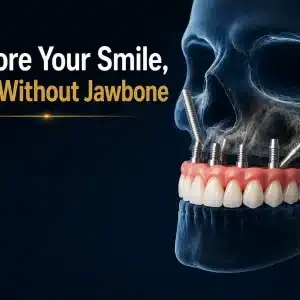

4. Zygomatic Implants:

Zygomatic implants are a specialized type of dental implant designed for patients who have severe bone loss in the upper jaw, particularly in the area of the maxillary sinuses. Instead of anchoring into the jawbone, zygomatic implants are anchored in the dense zygomatic bone, which provides exceptional stability and support. This approach eliminates the need for bone grafting procedures and allows for the immediate placement of prosthetic teeth, offering a quicker and more efficient treatment option for eligible patients.